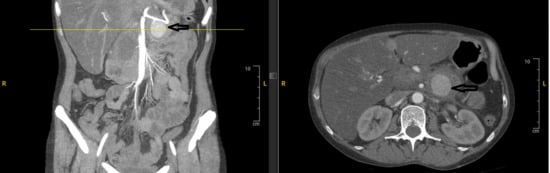

Over the next three months, she had recurrent admissions for alcohol-induced pancreatitis (peak lipase 527 U/L). She continued drinking heavily and developed alcoholic hepatitis (AST 400 U/L, INR 4.0), pulmonary embolism, and reduced left ventricular ejection fraction (45–50%). Serial CT imaging was conducted up to 3 months post-embolization: On 11 July 2024, there were sequelae of prior embolization with interval decrease in pseudocyst size to approximately 3 cm, mild pancreatic edema, and surrounding inflammatory stranding; on 15 July 2024, the pseudocyst measured 3.6 × 2.6 cm with embolization coils causing artifacts; on 15 August 2024, the pseudocyst was thick-walled and well-defined with internal debris, measuring 5.4 × 5.0 cm; on 12 September 2024, the pseudocyst decreased to 1.9 cm with high density, mild proximal pancreatic ductal dilatation, limited splenic vein evaluation due to metallic streak artifact, and no evidence of significant aneurysm recanalization. However, long-term surveillance lapsed due to patient non-compliance. Eight months after the initial embolization, the patient was found unresponsive and in pulseless electrical activity arrest. Return of spontaneous circulation was achieved, but she remained critically hypotensive (blood pressure 61/34 mmHg). Laboratory evaluation revealed severe metabolic acidosis (lactate 19.7 mmol/L), hemoglobin 6.4 g/dL, and lipase 118 U/L. Emergency exploratory laparotomy was initiated within 1–2 h of hospital arrival following resuscitation and revealed massive hemoperitoneum due to rupture of the previously embolized splenic artery pseudoaneurysm (likely via recanalization of the embolized site). The splenic artery was ligated, and a massive transfusion protocol was implemented, which amounted to over 55 units of blood products. Despite aggressive resuscitative measures and surgical intervention, her course was complicated by refractory shock, anuric acute kidney injury, disseminated intravascular coagulation (DIC), and multi-organ failure. After discussions with her family regarding her poor prognosis, care was transitioned to comfort measures, and she subsequently died.